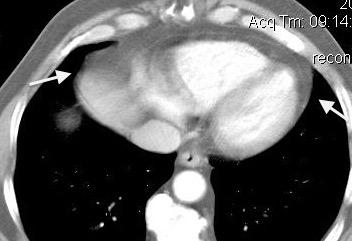

La ocupación del espacio pleural por derrame (o obstrucción aérea) se acomoda con expansión aumentada de la caja torácica, especialmente en eje vertical. La consecuencia es aplanamiento e incluso inversión diafragmática.

Afzal S, Fatima K, Ambareen M. Antenatal ultrasound diagnosis of congenital high airway obstruction syndrome: a case report and review of literature. Cureus. 2019. Thoma R et al. Physiology of breathlessness associated with pleural effusions. Curr Opin Pulm Med. 2015

Wang JS et al. Changes in pulmonary mechanics and gas exchange after thoracentesis on patients with inversion of a hemidiaphragm secondary to large pleural effusion . Chest 1995

Mesotelioma epitelioide